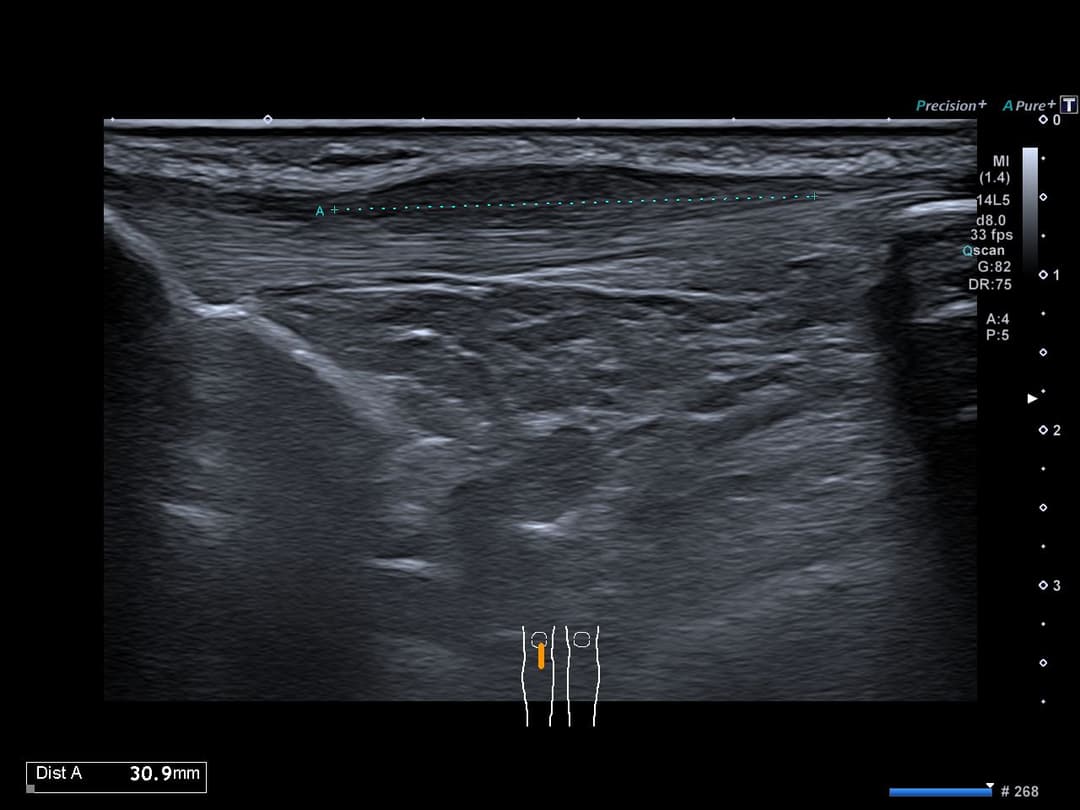

Tendinopathie patellaire corporéale superficielle

Échographie

Epaississement fusiforme avec hypo échogénicité de la portion corporéale superficielle du tendon patellaire, étendue sur 3cm de hauteur, sans fissuration intra-tendineuse notable.

Discret œdème des tissus mous cellulo-graisseux sous-cutanés adjacents.